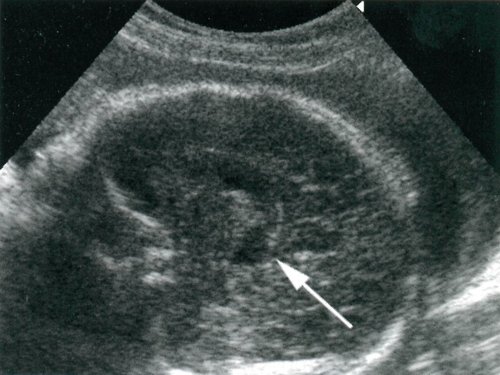

Рис. 2. Беременность 23 недели. Порок Арнольда-Киари II типа. Вид задней черепной ямки у плода после элиминации (отмечено стрелками).

Рис. 5. Беременность 23 недели. Порок Арнольда-Киари II типа. Расширенные задние отделы 3-го желудочка (отмечено стрелкой).